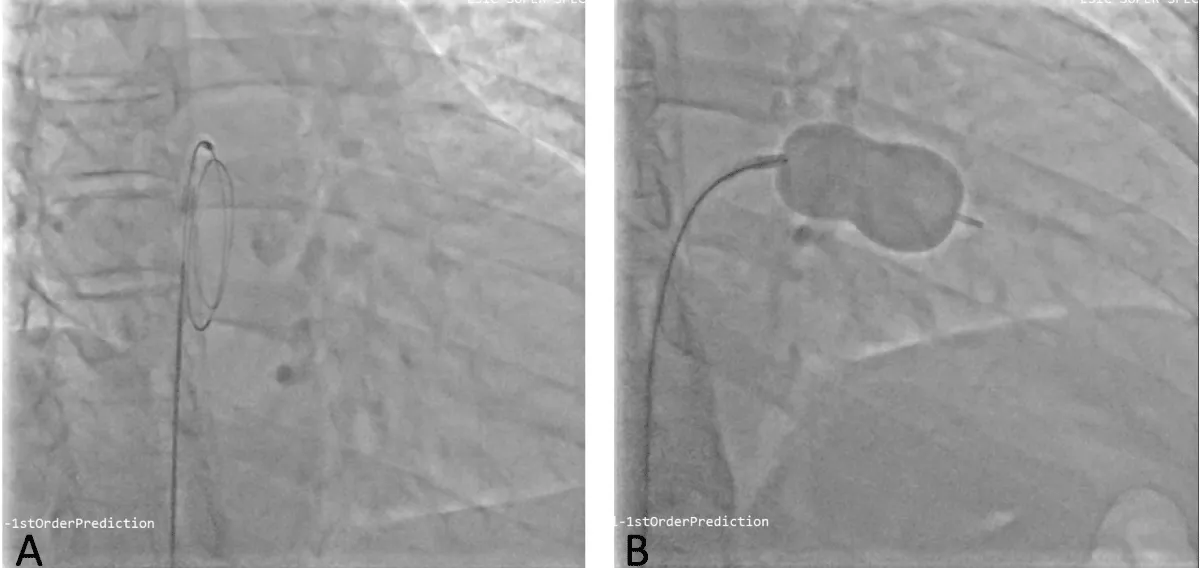

He was planned for double valve replacement (DVR), but the patient declined due to the high surgical risk. Therefore, he was considered for staged BMV and Transcatheter aortic valve replacement (TAVR). Pre-procedural planning was done for TAVR, and after ensuring the patency and adequacy of femoral vessels, he underwent a coronary angiogram (CAG), which showed normal coronaries. Following consent, the right femoral vein was accessed. A transseptal puncture was performed with a broken Brough needle, and the LA wire was parked. The MV was dilated with a 26 mm Inoue balloon (Figure 7), resulting in a reduction of the MV gradient from 24/10 mm Hg to 9/5 mm Hg and an increase in MV area from 0.9 cm2 to 1.6 cm2. There were no post-procedural complications. After 1 month, he underwent TAVI. Both right and left femoral artery access was obtained. Following pre-dilatation of the AV with an 18 mm balloon, TAVR was performed using a 26 mm balloon-expandable valve (Myval, Meril Lifesciences, Vapi, Gujarat, India) (Figure 8) (Video 3), followed by post-dilatation under accelerated right ventricular pacing (180 bpm). ECHO and final aortography showed no paravalvular leakage after device release (Figure 9).

Figure 7: Fluoroscopic image of LA wire passed through atrial septal puncture (A) and Balloon dilatation of the mitral valve with Inoue balloon (B).